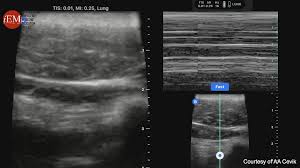

경동맥 초음파 검사 과정과 소요시간

진행 과정은 다음과 같아 매우 간단합니다.

- 편안하게 누운 상태에서 목 오른쪽, 왼쪽을 노출

- 젤을 바른 후 초음파 탐촉자를 경동맥 위에 대고 영상 관찰

- 혈류 속도 측정과 플라크 유무 확인

- 검사 시간: 보통 10~20분 내외

- 검사 후 일상생활 즉시 가능

금식이 필요 없으며, 통증과 부작용이 거의 없어 부담 없이 받을 수 있는 검사입니다.